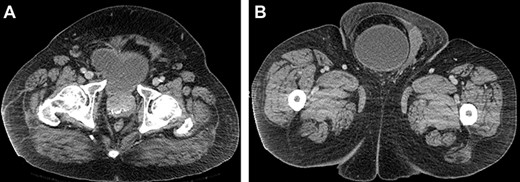

Computed tomography (CT) scan of the abdomen and pelvis with contrast revealed a large right indirect inguinal hernia containing a significant portion of the bladder within the scrotum (Figs 1–3). There was associated bilateral hydronephrosis and hydroureter, and significant scrotal oedema seen within the soft tissues.

Coronal CT image of the abdomen and pelvis demonstrating herniation of the bladder through the inguinal canal into the scrotum, with associated oedema of the scrotal soft tissues.